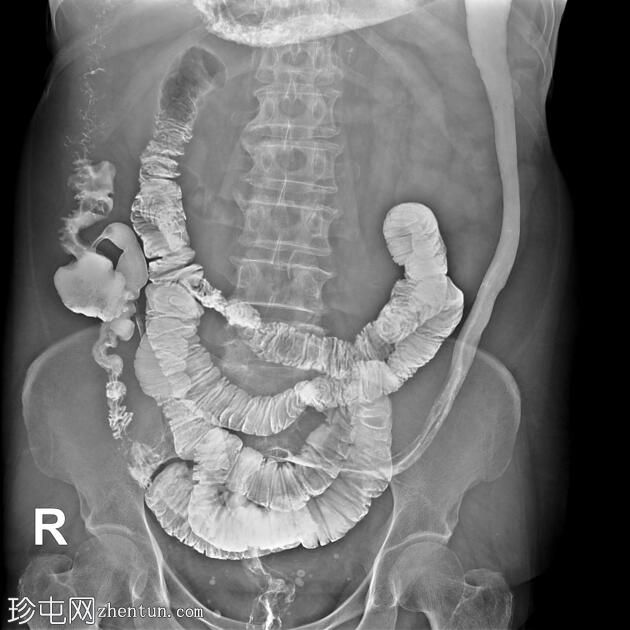

结肠异常表现包括结肠袋皱襞消失,使其外观模糊,呈铅管样改变。

其他异常表现包括降结肠和乙状结肠肠袢狭窄,以及横结肠和降结肠多处黏膜糜烂(双对比增强图像可见)。

未见肿块或瘘管形成。

升结肠外观正常,结肠袋皱襞完整。

结肠呈铅管状外观是慢性炎症性肠病(溃疡性结肠炎)的典型放射学表现。